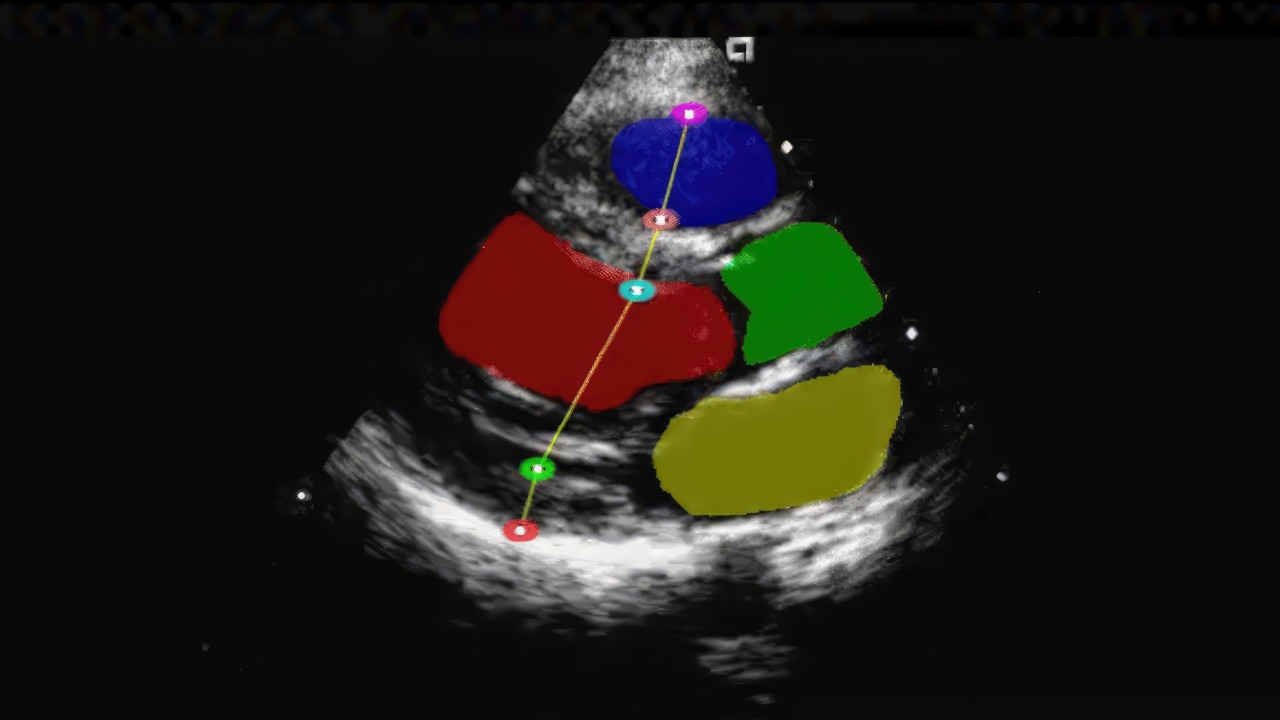

NVIDIA Holoscan is a versatile edge AI computing platform for real-time processing of streaming medical device data.

Medical device and AI application developers building medical device computing systems for platforms and sensor frontends can use Holoscan to build real-time AI at the clinical edge.

The platform provides an accelerated, full-stack infrastructure that enables real-time AI processing, seamless sensor integration, and rapid development of medical solutions at the clinical edge.

NVIDIA Holoscan Reference Applications and operators provide ready-to-use, customizable examples and components for building real-time, AI-driven sensor processing applications.

Medical device and AI developers looking to accelerate their development can use Holoscan Reference Applications to quickly build and deploy solutions across medical imaging, sensor processing, and edge computing.

Holoscan reference applications significantly reduce development time and complexity, leveraging diverse contributions from both NVIDIA and its partner ecosystem to bring a diverse collection of workflows and operators to its open repository.